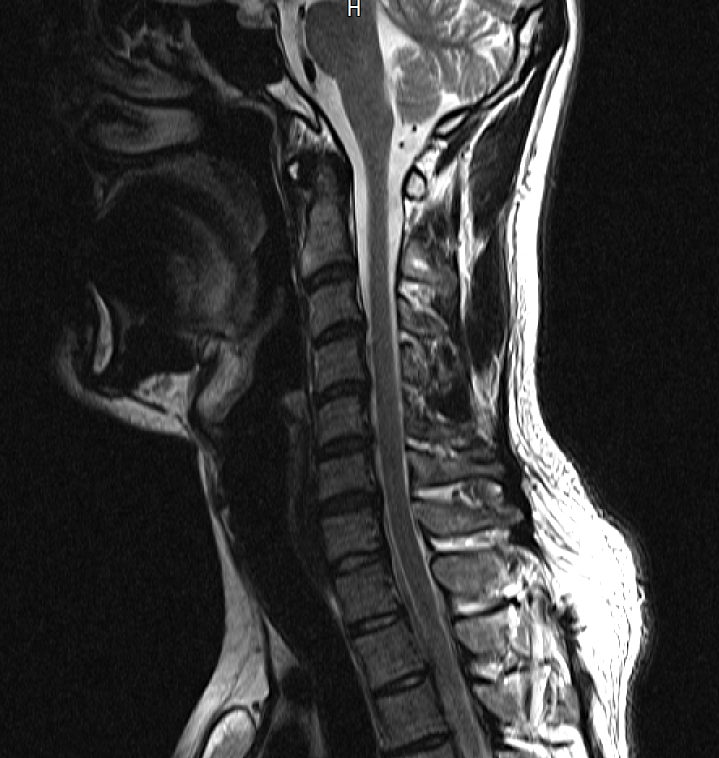

아래는 저의 경추과 요추 MRI 사진 첨부합니다.

• 1번 째 사진

• 2번 째 사진

목디스크로 인해 상하지의 힘이 다 빠지려면 척수까지 침범하는 병변이 있어야 합니다.

그런 상황이 아니므로 디스크는 배제해도 되겠습니다.